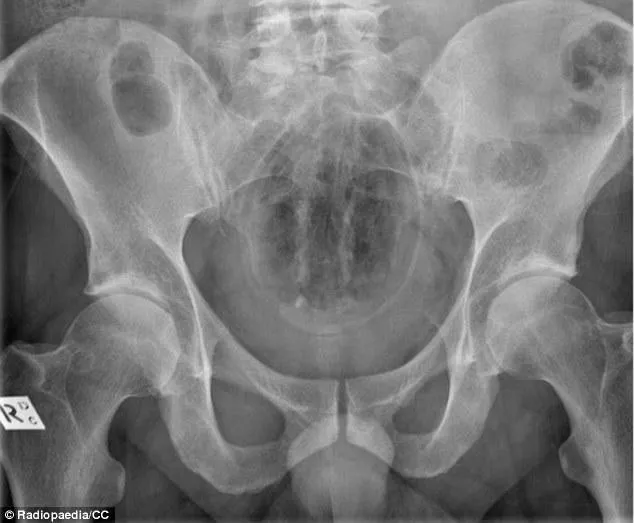

Le patient aurait avoué s"être lui-même inséré cette petite bouteille contenant du café d"une marque très connue, dans le rectum. Comment les aiguilles se sont retrouvées plantées à l"intérieur ? C"est encore un mystère.